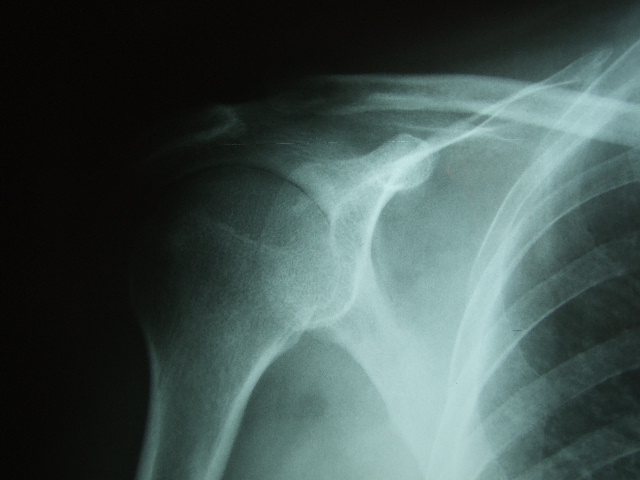

APR Luxación de hombro